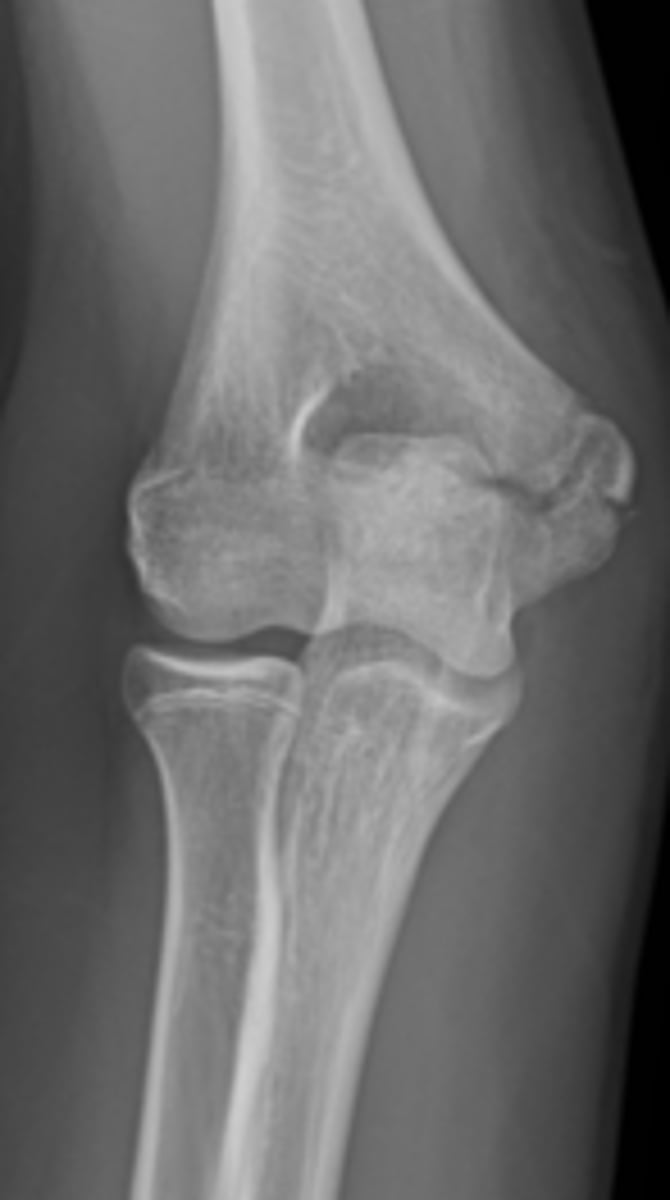

What type of fracture is this?

answer

Supracondylar Fracture

While moonlighting in the emergency department of a small community hospital, you examine a 25-year-old man who fell on an outstretched

hand and now complains of elbow pain. You obtain an AP and lateral view of his elbow (lateral view of the elbow).

You first examine the lateral view of the elbow in Case

6-3 (Figure 6-10). You find

A. a lytic lesion in the distal humerus.

B. displacement of the fat pads of the elbow.

C. a fracture through the proximal ulna.

D. dislocation of the elbow.

B.

You have the anterior sail sign and posterior fat pad sign.